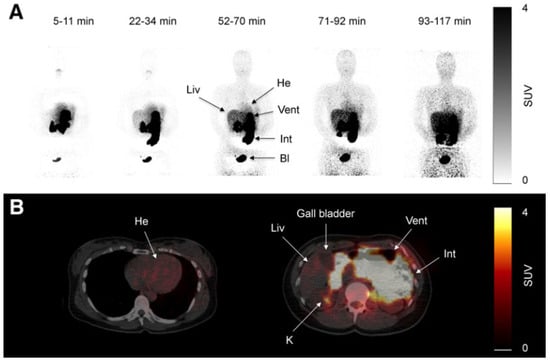

C11-metformin (9.5 microSv/MBq = ca.1.1 micrograms), first injected intravenously, allowed the study of its biodistribution in humans by the PET scan technique [133]. Most of the activity was found in the liver, the kidneys, and the urinary bladder. Most of the absorbed compound was cleared from the blood 20 min after injection. Dosimetry calculations were performed for the stomach-, small intestine-, liver-, kidney-, and bladder contents. It was demonstrated that hepatic metformin uptake is very rapid and fully reversible, but the accumulation of the activity was higher than after intravenous administration since, although slower, the tracer delivery came from the portal blood through the liver first. Two hours after the oral ingestion of the tracer, the bulk of the radioactivity was still found in the intestine (Figure 1 lower panel), and no further observation of the fate of the radioactive metformin was possible.

Scans of C11-metformin administered to humans intravenously and orally (upper (A) and lower (B) panel, respectively) taken at different times after administration. Gormensen LC et al. ([133], with permission).

The kidney-to-blood activity ratio was identical independently of the administration route of the radioactive metformin. Some discrete uptakes of the tracer was found in the salivary glands, and discrete uptake was found also in the intestine. No activity was found in the gallbladder. Significant amounts of the tracer passed to the small intestine 10 min after ingestion.